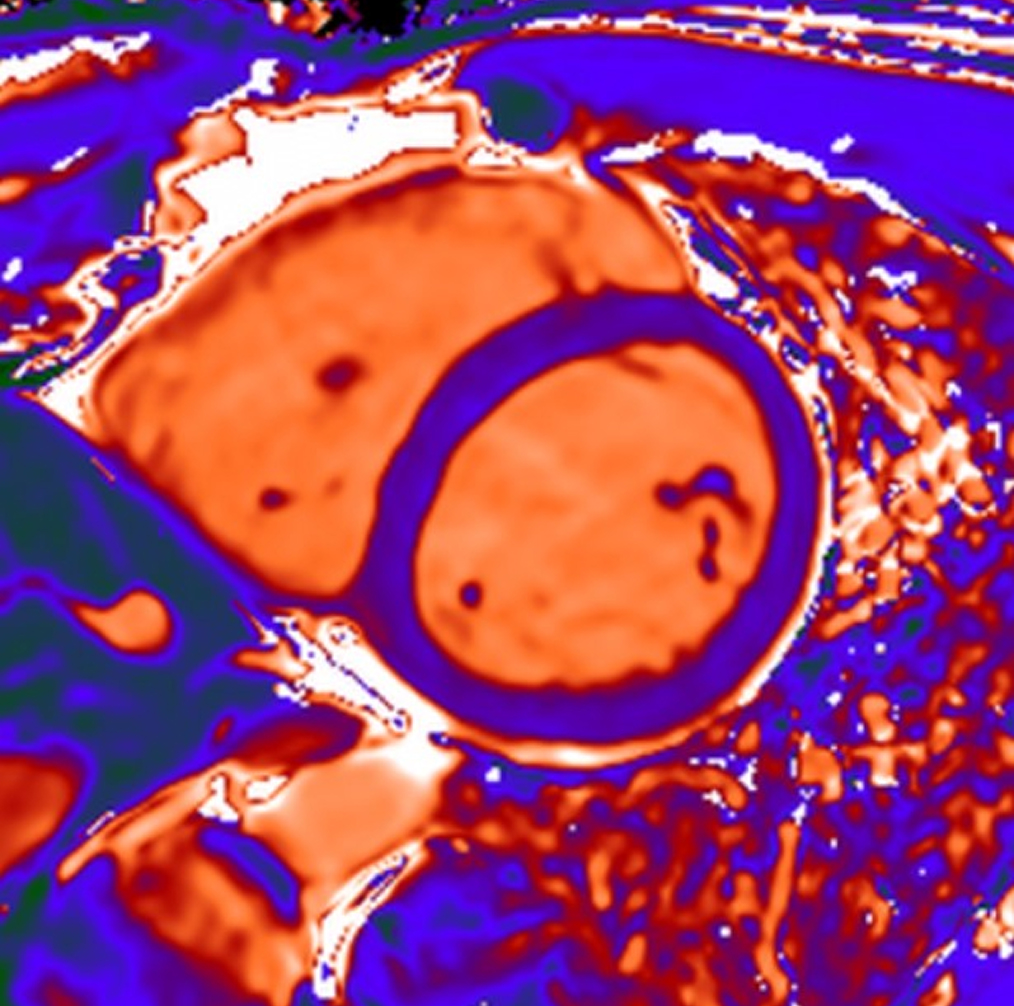

There is a world outside the stent mesh

Caso condiviso da Saima Mushtaq

Paziente con anamnesi di malattia coronarica e pregresso impianto di stent sulla discendente anteriore sinistra.

Per prima cosa, esamina l'intera scansione. Concentrati sul tronco comune e sulla porzione prossimale della discendente anteriore sinistra.